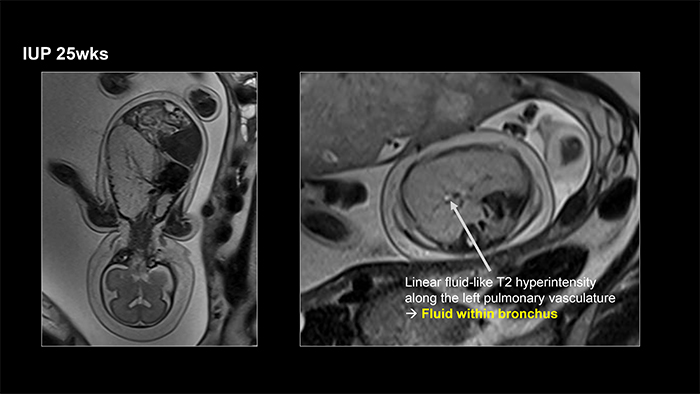

Based on these findings, congenital pulmonary airway malformation (CPAM) or unilateral bronchial atresia was suspected. At 25 weeks of gestation, magnetic resonance imaging confirmed a diagnosis of left unilateral bronchial atresia.

Unlike congenital high airway obstruction syndrome (CHAOS), which typically presents with symmetrically enlarged both lungs and increased echogenicity, unilateral bronchial atresia results in massive enlargement of only one lung.

This condition may mimic more commonly encountered unilateral fetal lung abnormalities, particularly microcystic CPAM or pulmonary sequestration.